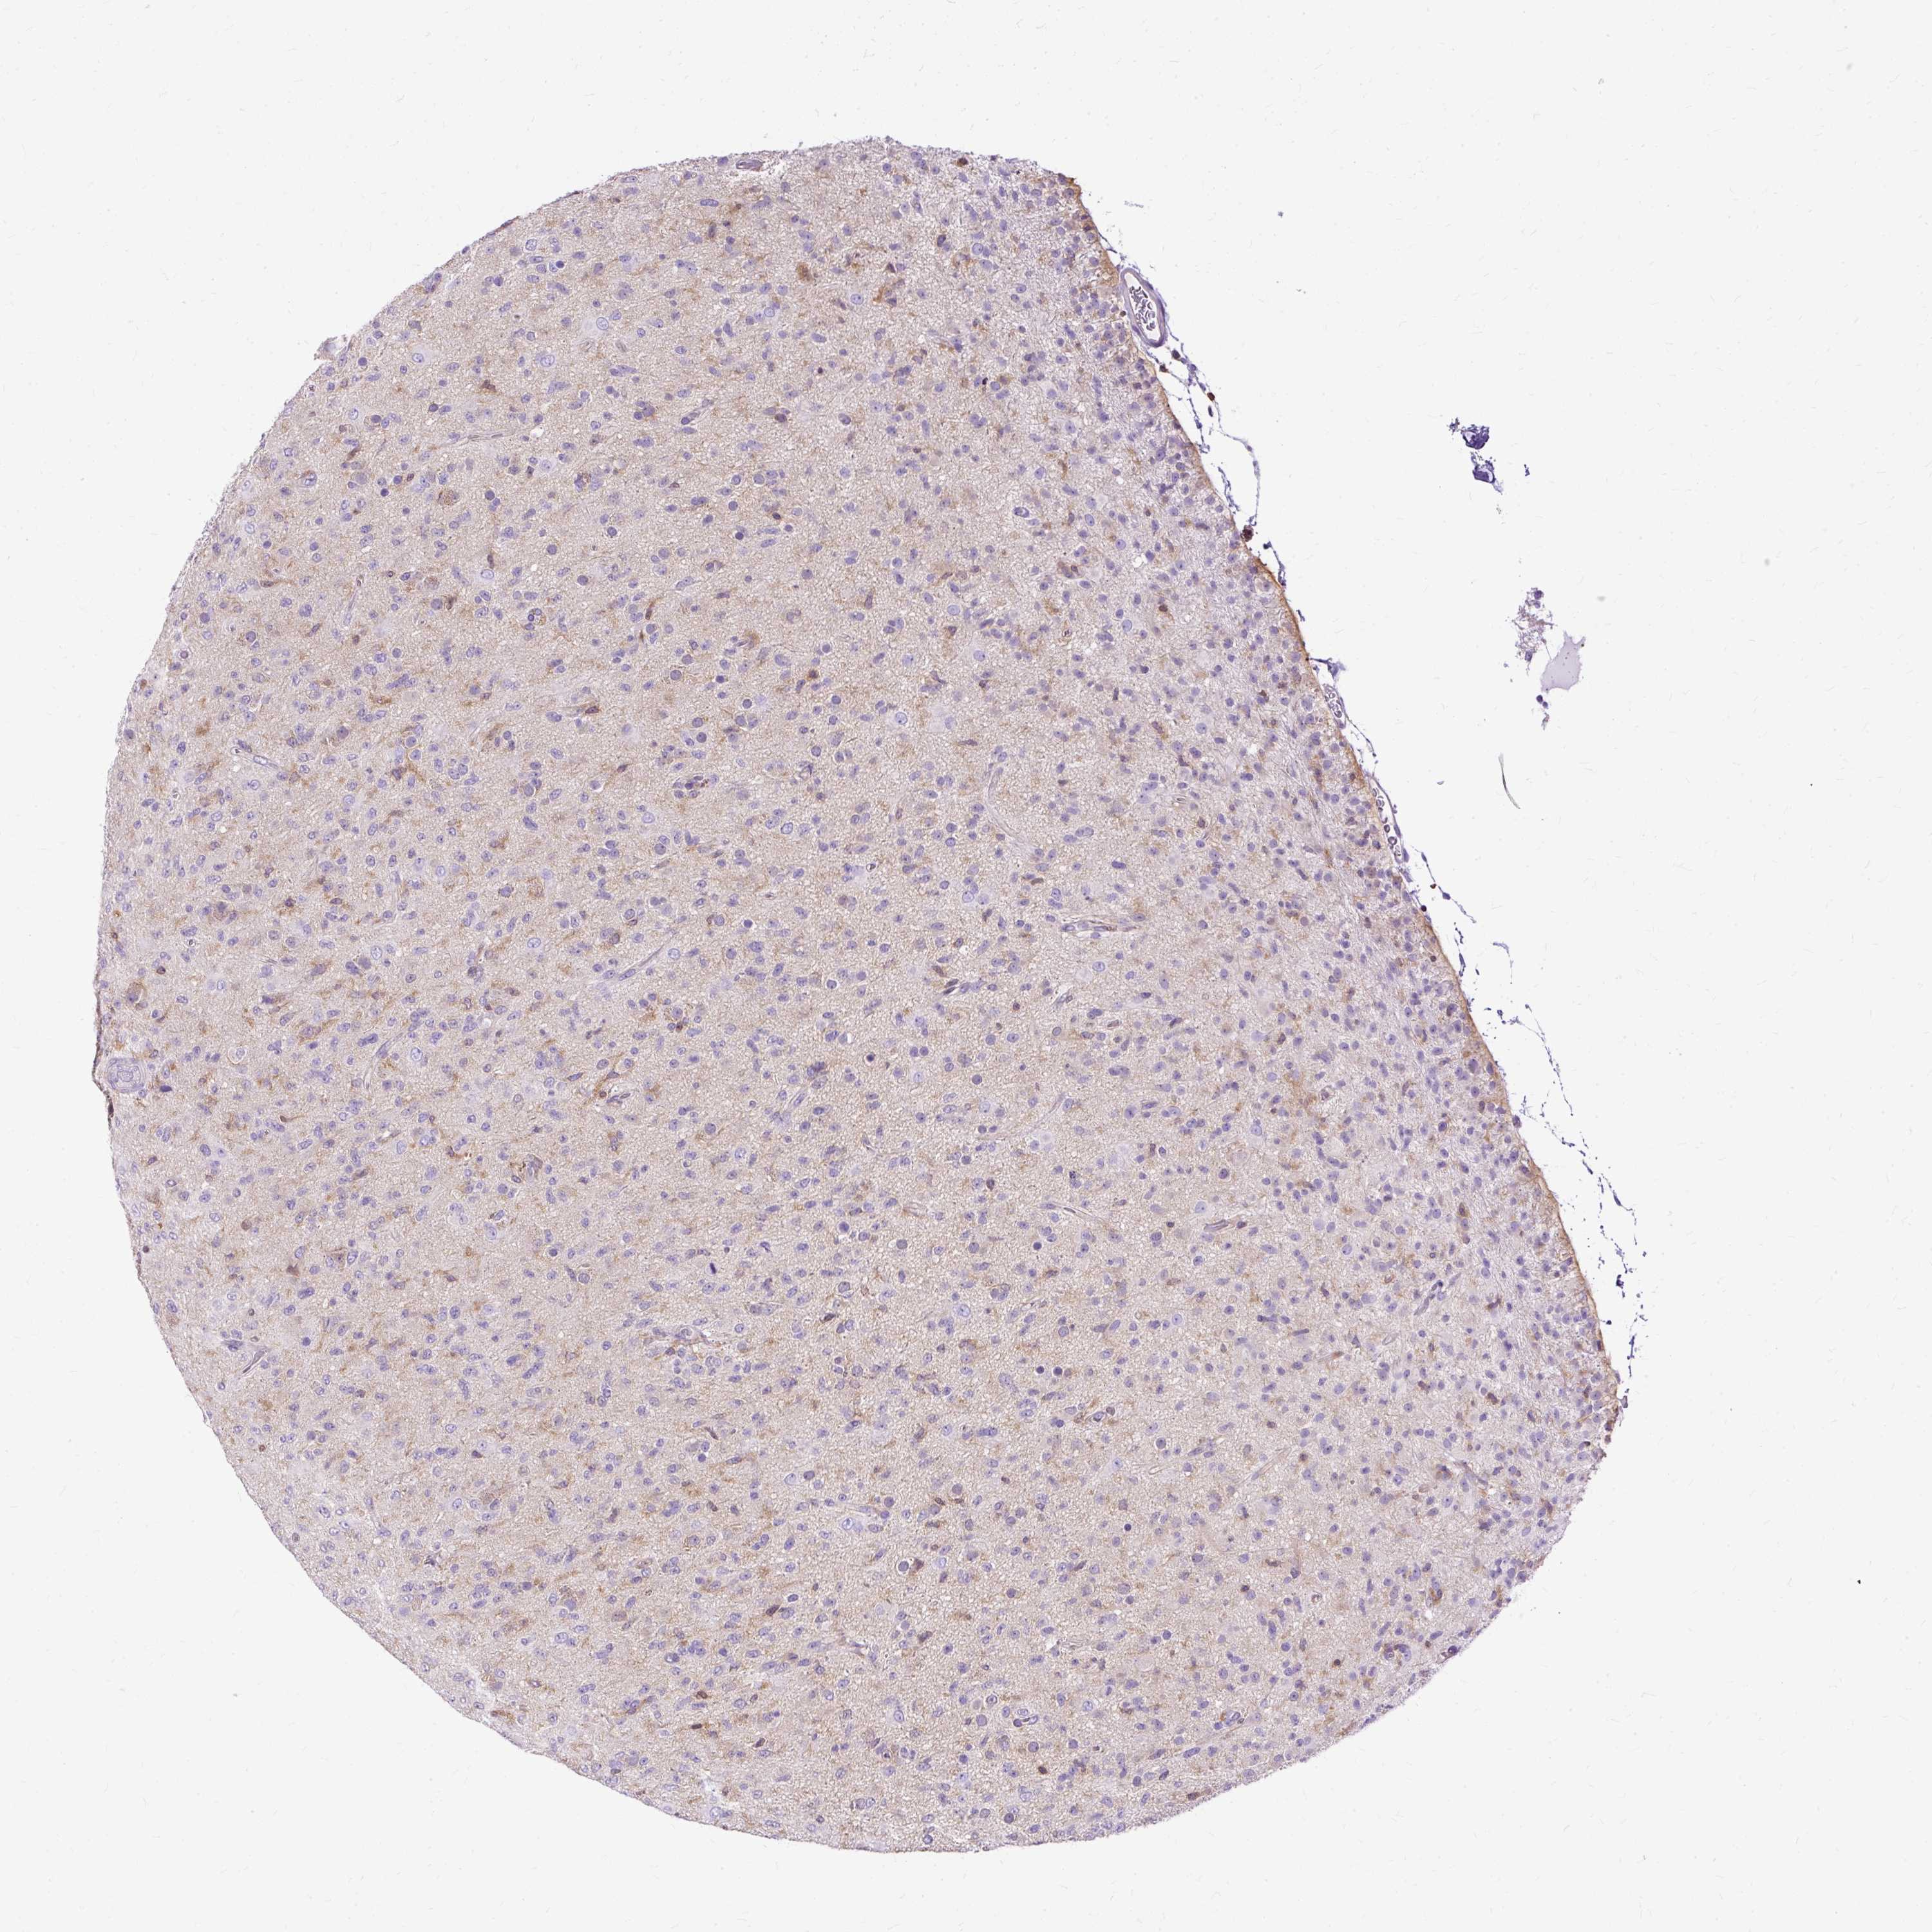

GLIOMA - Protein expressioni

A mouse-over function shows sample information and annotation data. Click on an image to view it in a full screen mode. Samples can be filtered based on level of antibody staining by selecting one or several of the following categories: high, medium, low and not detected. The assay and annotation is described here.

Note that samples used for immunohistochemistry by the Human Protein Atlas do not correspond to samples in the TCGA dataset.

Antibody stainingi

Antibody staining in the annotated cell types in the current human tissue is reported as not detected, low, medium, or high, based on conventional immunohistochemistry profiling in selected tissues. This score is based on the combination of the staining intensity and fraction of stained cells.

Each image is clickable and will lead to virtual microscopy that enables deeper exploration of all samples and also displays staining intensity scores, fraction scores and subcellular localization as well as patient and tissue information for each sample.

Antibody HPA053874

Staining

High

Medium

Low

Not detected

Intensity

Strong

Moderate

Weak

Negative

Quantity

>75%

75%-25%

<25%

None

Location

Nuclear

Cytoplasmic/membranous

Cytoplasmic/membranous,nuclear

Glioma, malignant, Low grade

Glioma, malignant, High grade